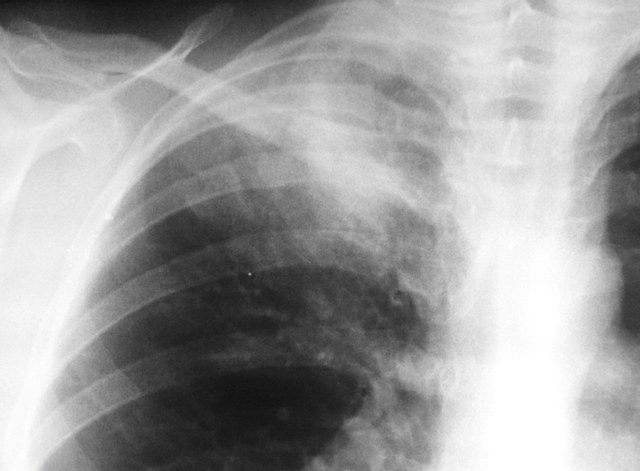

Женщина 32 года; месяц как кашляет. Повышения температутры тела не отмечала. Изначально выполнили рентгенографию. Что делать дальше?

Ок, мы определились с дифференциальным рядом при такой рентгенологической картине (Затемнение верхених сегментов правого лёгкого, S2). Какую рекоммендацию Вы бы дали такому пациенту? Что будем делать дальше?

Далее рекомендуем лабораторные исследования, КТ легких.

Давайте определимся, для начала обозначим какие КТ признаки мы видим на представленных сканах. И главное это не перечисление вариантов диагнозов (если нет однозначного варианта); а определить что надо сделать следующим этапом для достижения окончательного диагноза.

Вполне адекватная тактика. КТ контроль через 3-4 недели после антибактериальной терапии, совершенно правильно.

В данном случае, пульмонолог решил пойти на бронхоскопию; был забор материала. Лабараторный анализ (ПЦР) выявил положительную реакцию на туберкулёз.